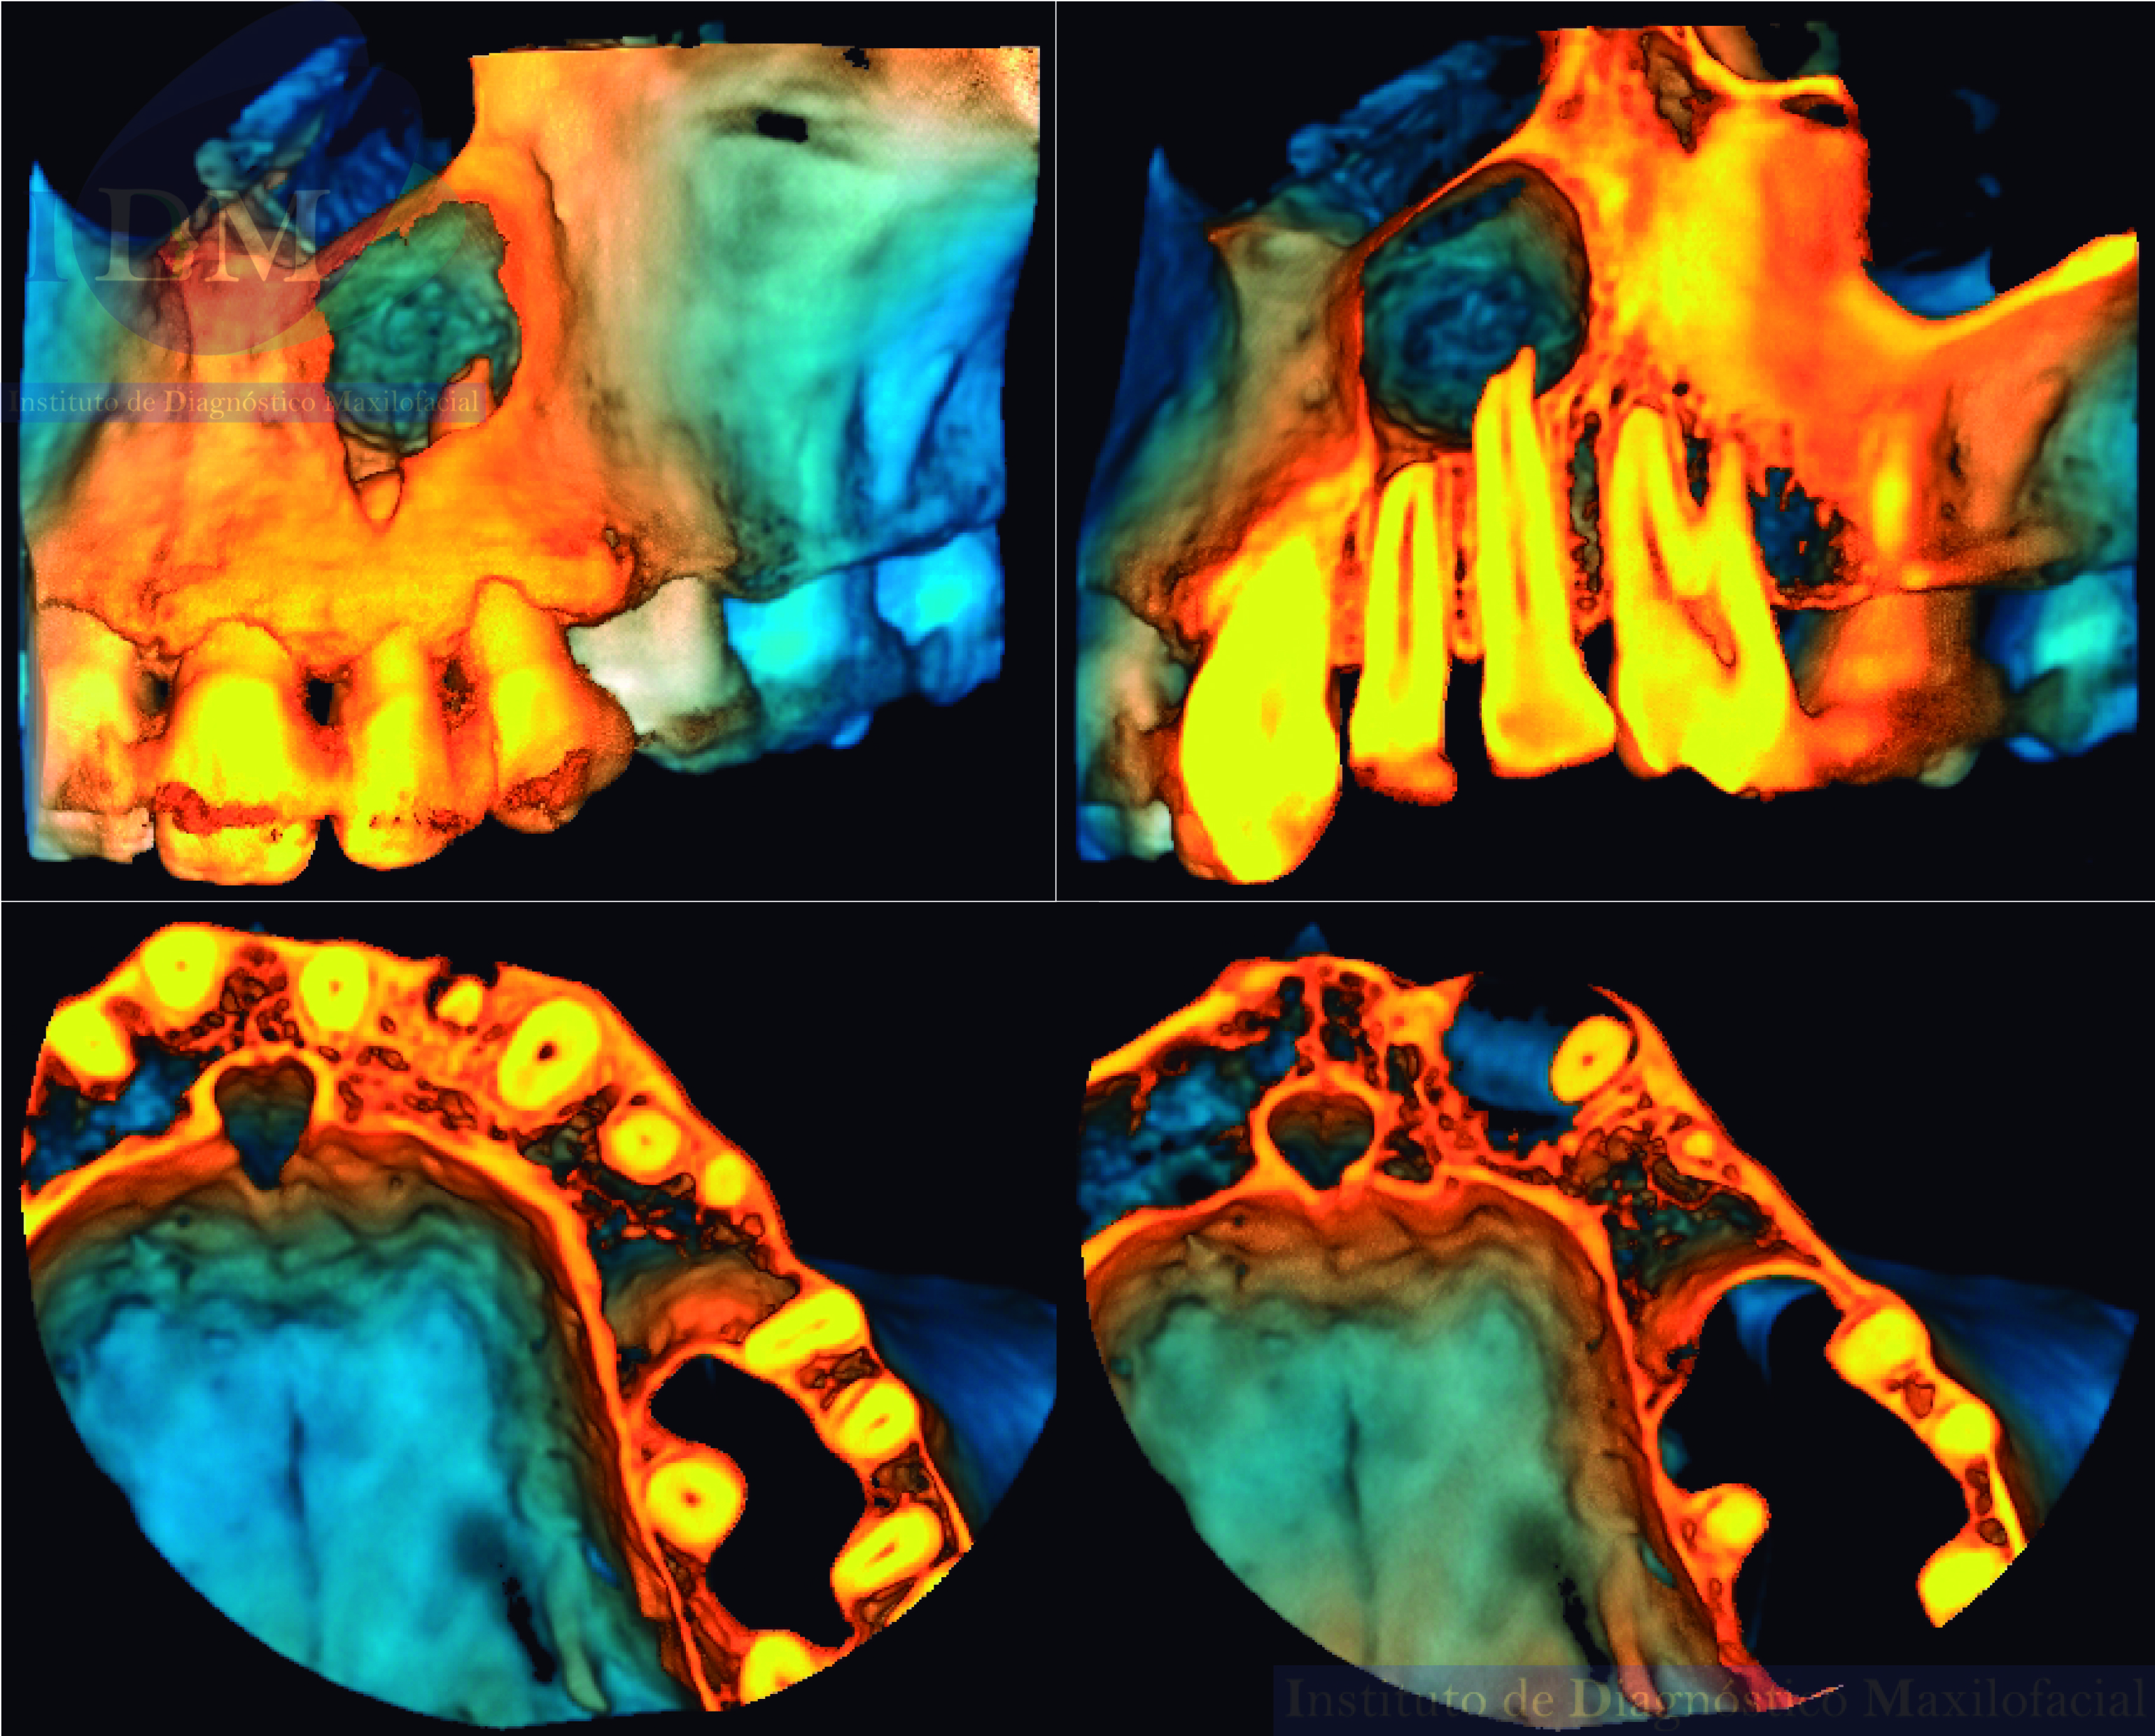

En las reconstrucciones 3D se representa de manera didáctica el compromiso que tiene la lesión con las estructuras adyacentes. (Figura 4).

RECONSTRUCCIÓN 3D